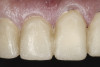

(38.) Postoperative right anterior, close-up view.

Figure 38

(39.) Postoperative anterior, close-up view.

Figure 39